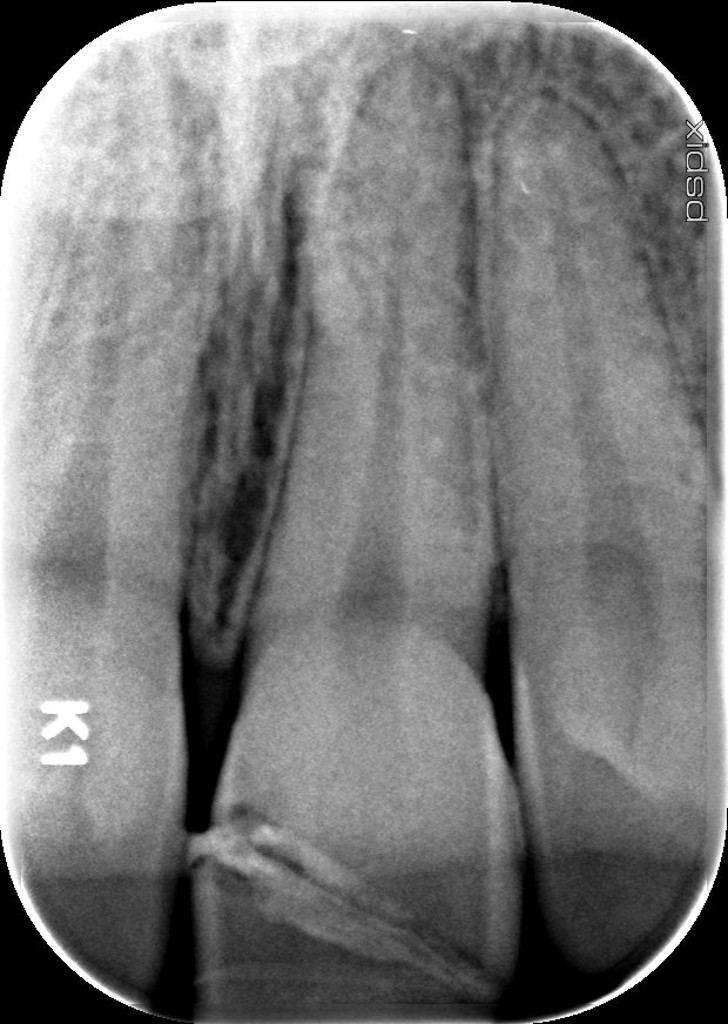

Radiographie pré-op